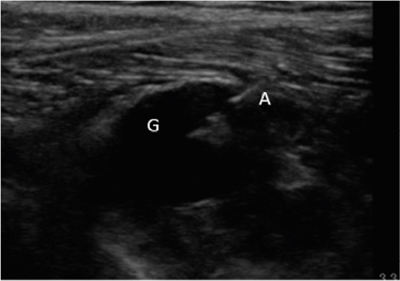

Neuropatía peronea secundaria a ganglión extraneural: revisión de literatura y propuesta de tratamiento. Caso no positivo

Peroneal neuropathy caused by an extraneural ganglion: literary review and treatment proposal. A non-positive case

Este artículo presenta el caso de un paciente de 69 años con una neuropatía compresiva peronea secundaria a un ganglión, inicialmente interpretada como una radiculopatía L5. Este incorrecto enfoque supuso la sobremedicación del paciente, un mal control algésico, la realización de una discectomía L4-L5 innecesaria y una pobre evolución neurológica.

Un enfoque diagnóstico correcto y un abordaje terapéutico precoz habrían supuesto una mayor mejoría clínica e incluso una recuperación neurológica completa del paciente. Por ello, este caso sirve para resaltar: a) el valor de la ecografía en neuropatías periféricas como herramienta diagnóstica y pronóstica y el de la ecografía en gangliones como arma diagnóstico-terapéutica; b) el uso de las pruebas diagnósticas como apoyo a una exploración física exhaustiva, y no como diagnóstico en sí mismas, y c) la importancia de la publicación de casos no positivos para optimizar recursos, evitar repetir errores, reducir el sesgo de publicación y facilitar el inicio de proyectos de investigación.

Figura 1